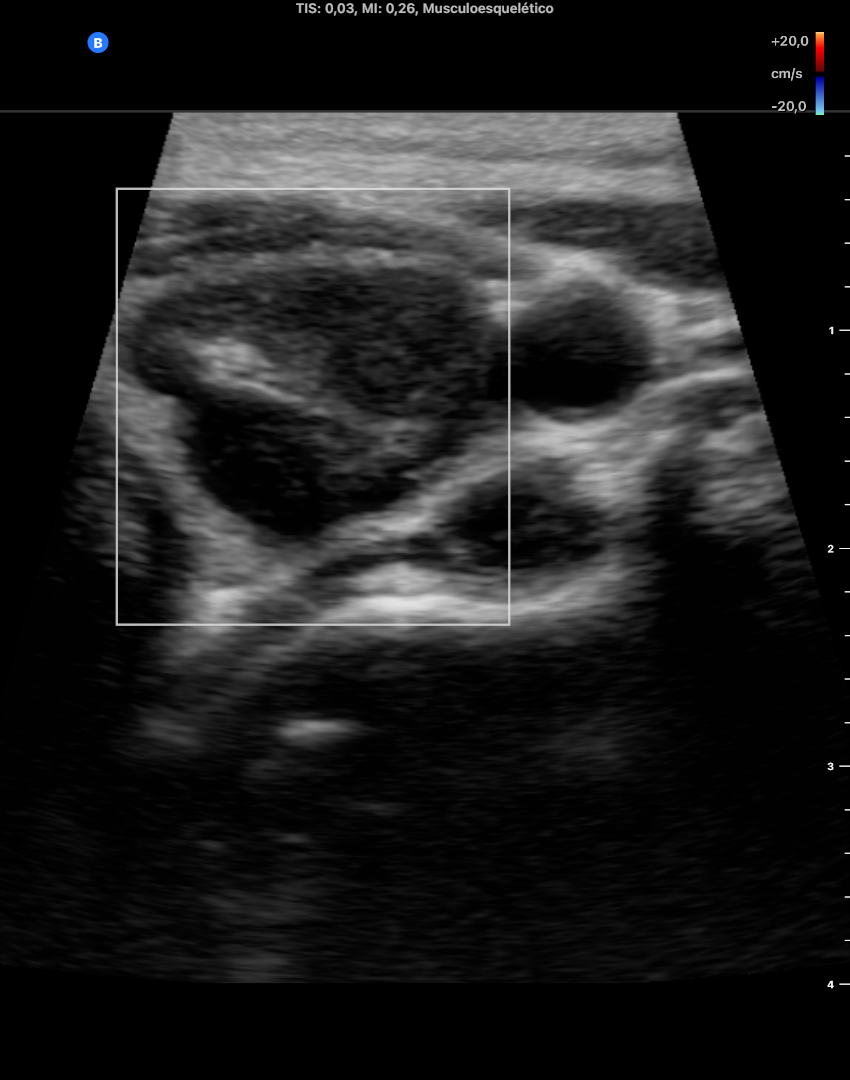

EcoscopiAP:

Tiroides de tamaño y ecoestructura normal que no capta Doppler.

En LTD se objetivan 2 nódulos, uno de ellos quistico y el otro solido bien delimitados, que no captan doppler de 2 x 3 x 2 mm cada uno aproximdamente en diametros APxTxL.

En LTI se objetiva un nódulo predominante de 30 mm de diámetro L y 16 x 14 mm en diámetros APxT captante de Doppler, de contenido casi solido, TIRADS 4-5. No adenopatias laterocervicales sospechosas.